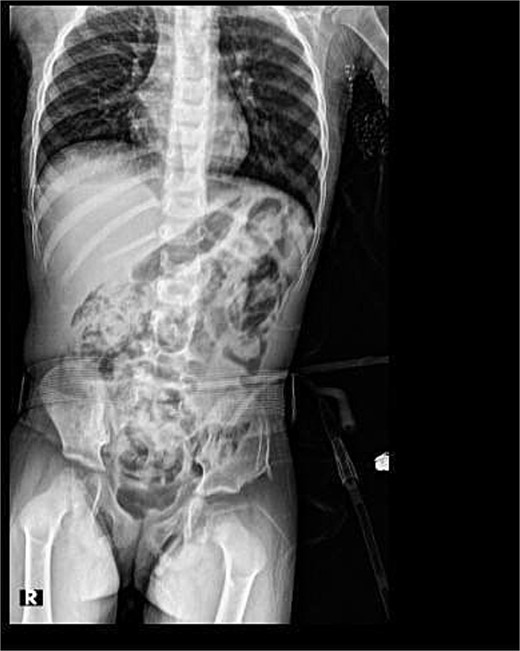

Antegrade and retrograde cystoscopy revealed a damaged urethra and cystitis (Fig. 1). The cystoscope passed smoothly through the suprapubic site, though it was difficult to navigate the urethra.

Her post-operative course was unremarkable. An evaluatory X-ray 3 days post-op revealed good outcomes (Fig. 2).